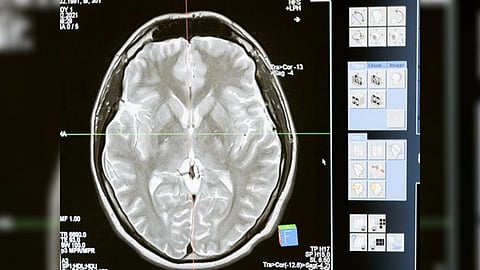

Protein-based biopharmaceuticals or biologics, such as antibodies, are promising therapeutic tools to specifically target clumps of protein found in neurodegenerative diseases such as Alzheimer's disease and Parkinson Disease.

However, the blood-brain barrier (BBB) provides a significant hurdle when trying to deliver biologics to areas of the brain to stop these large molecules causing disease.